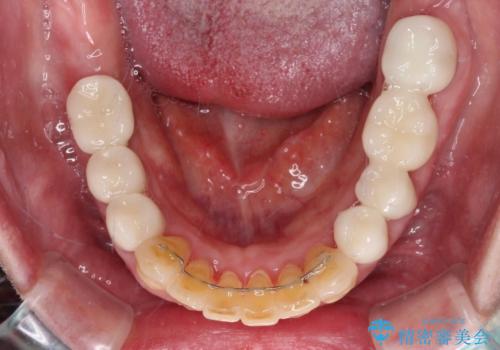

歯肉の状態が落ち着いた後に下顎の矯正治療を行い、その後補綴治療を行うこととしました。